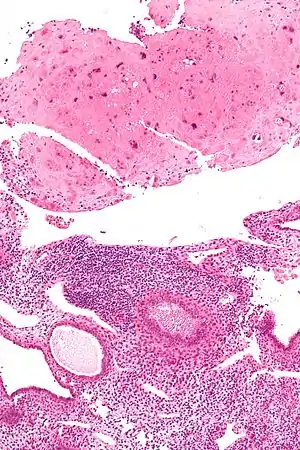

| Micrograph of a placental site nodule (top of image). H&E stain. | |

A placental site nodule (PSN) is a benign remnant from a previous pregnancy.[1]

PSNs are intermediate trophoblastic remnants.

Typically, they consist of pink (hyaline) material using the standard stain and contain few cells. Bizarre multinucleated cells may be present; however, there is no mitotic activity. The differential diagnosis includes (cervical) squamous cell carcinoma, gestational trophoblastic disease, and exaggerated placental site.